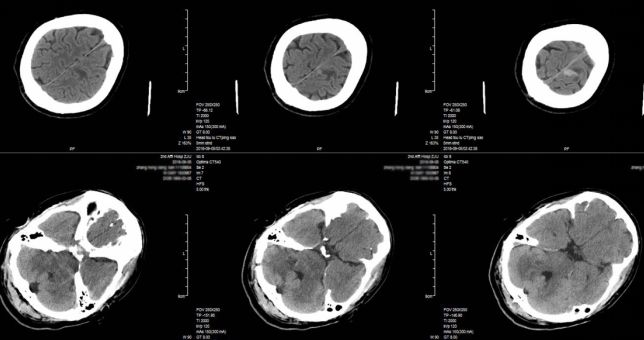

入院后第14日,患者意识水平下降,查体:昏睡状态,瞳孔左侧直径2mm,右侧直径3mm,对光反射迟钝,舌根后坠,肢端青紫,氧饱和度下降至80%,紧急联系气管插管转脑重症监护室。急诊头胸部CT检查,提示左额出现新发病灶(图7),肺部感染较前加重(图8)。

图7. 入院后第14天急诊复查患者头部CT提示左额顶叶出现新发病灶。